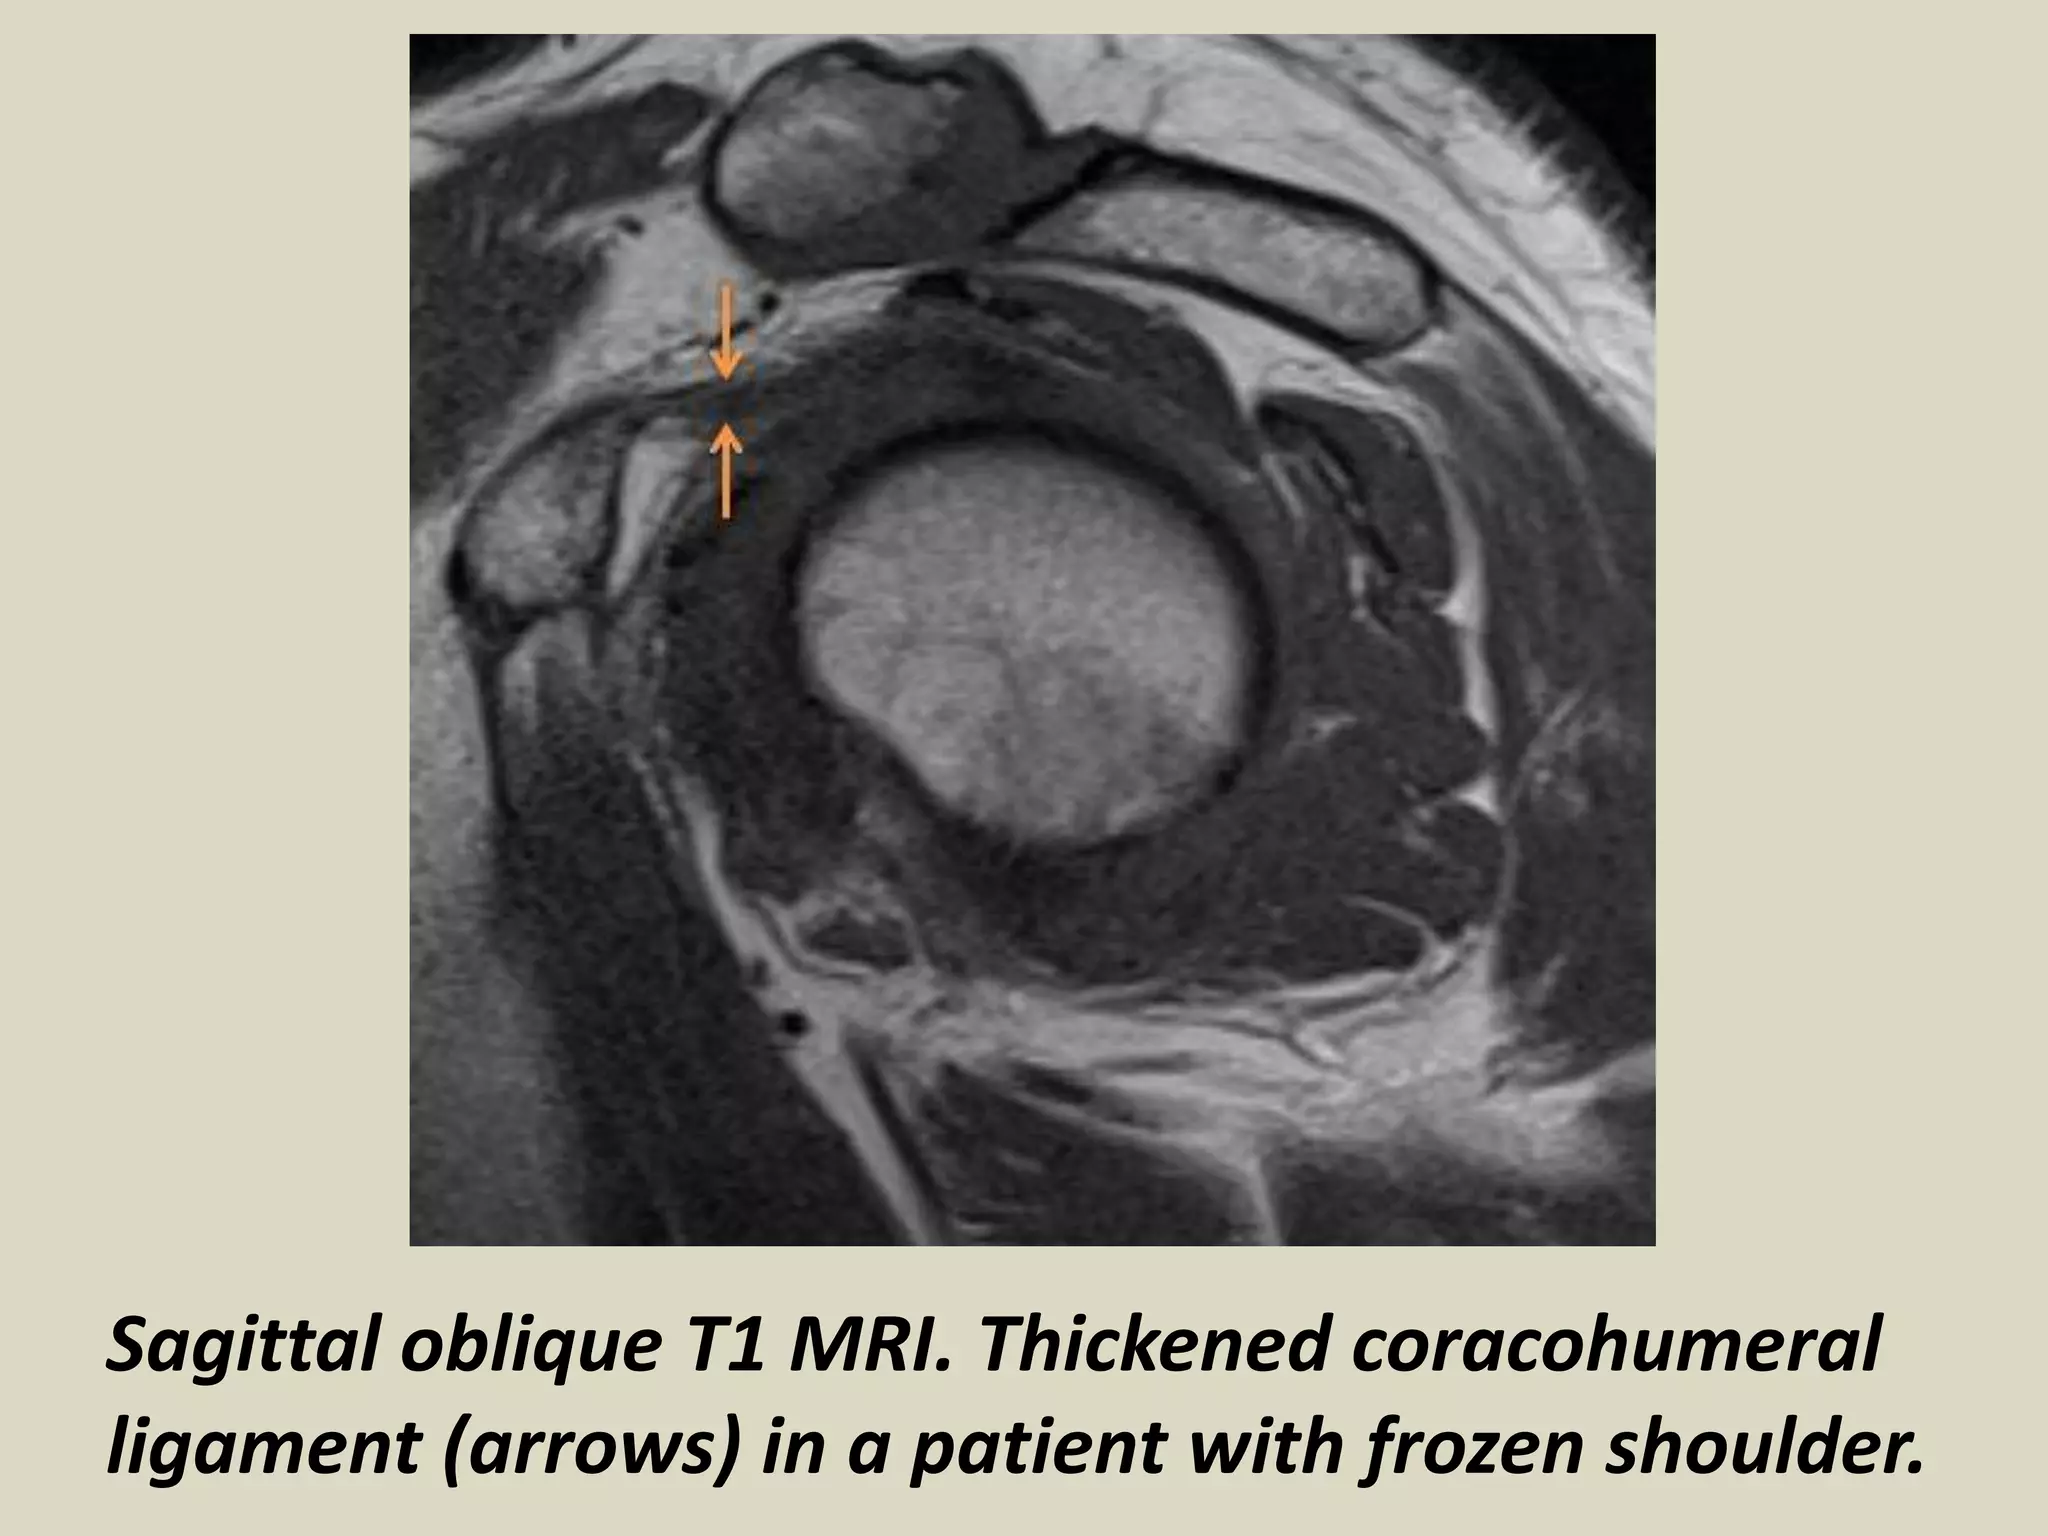

Coracohumeral Ligament Mri Frozen Shoulder Mri See the findings, diagnosis, discussion, and. Find out more about the signs and. Frozen shoulder can usually be diagnosed from signs and symptoms alone. Adhesive capsulitis (also known as frozen shoulder) is a condition of the shoulder characterized by functional loss of both passive and active shoulder motion commonly associated. Learn how to diagnose adhesive capsulitis or frozen shoulder on. Frozen Shoulder Mri.